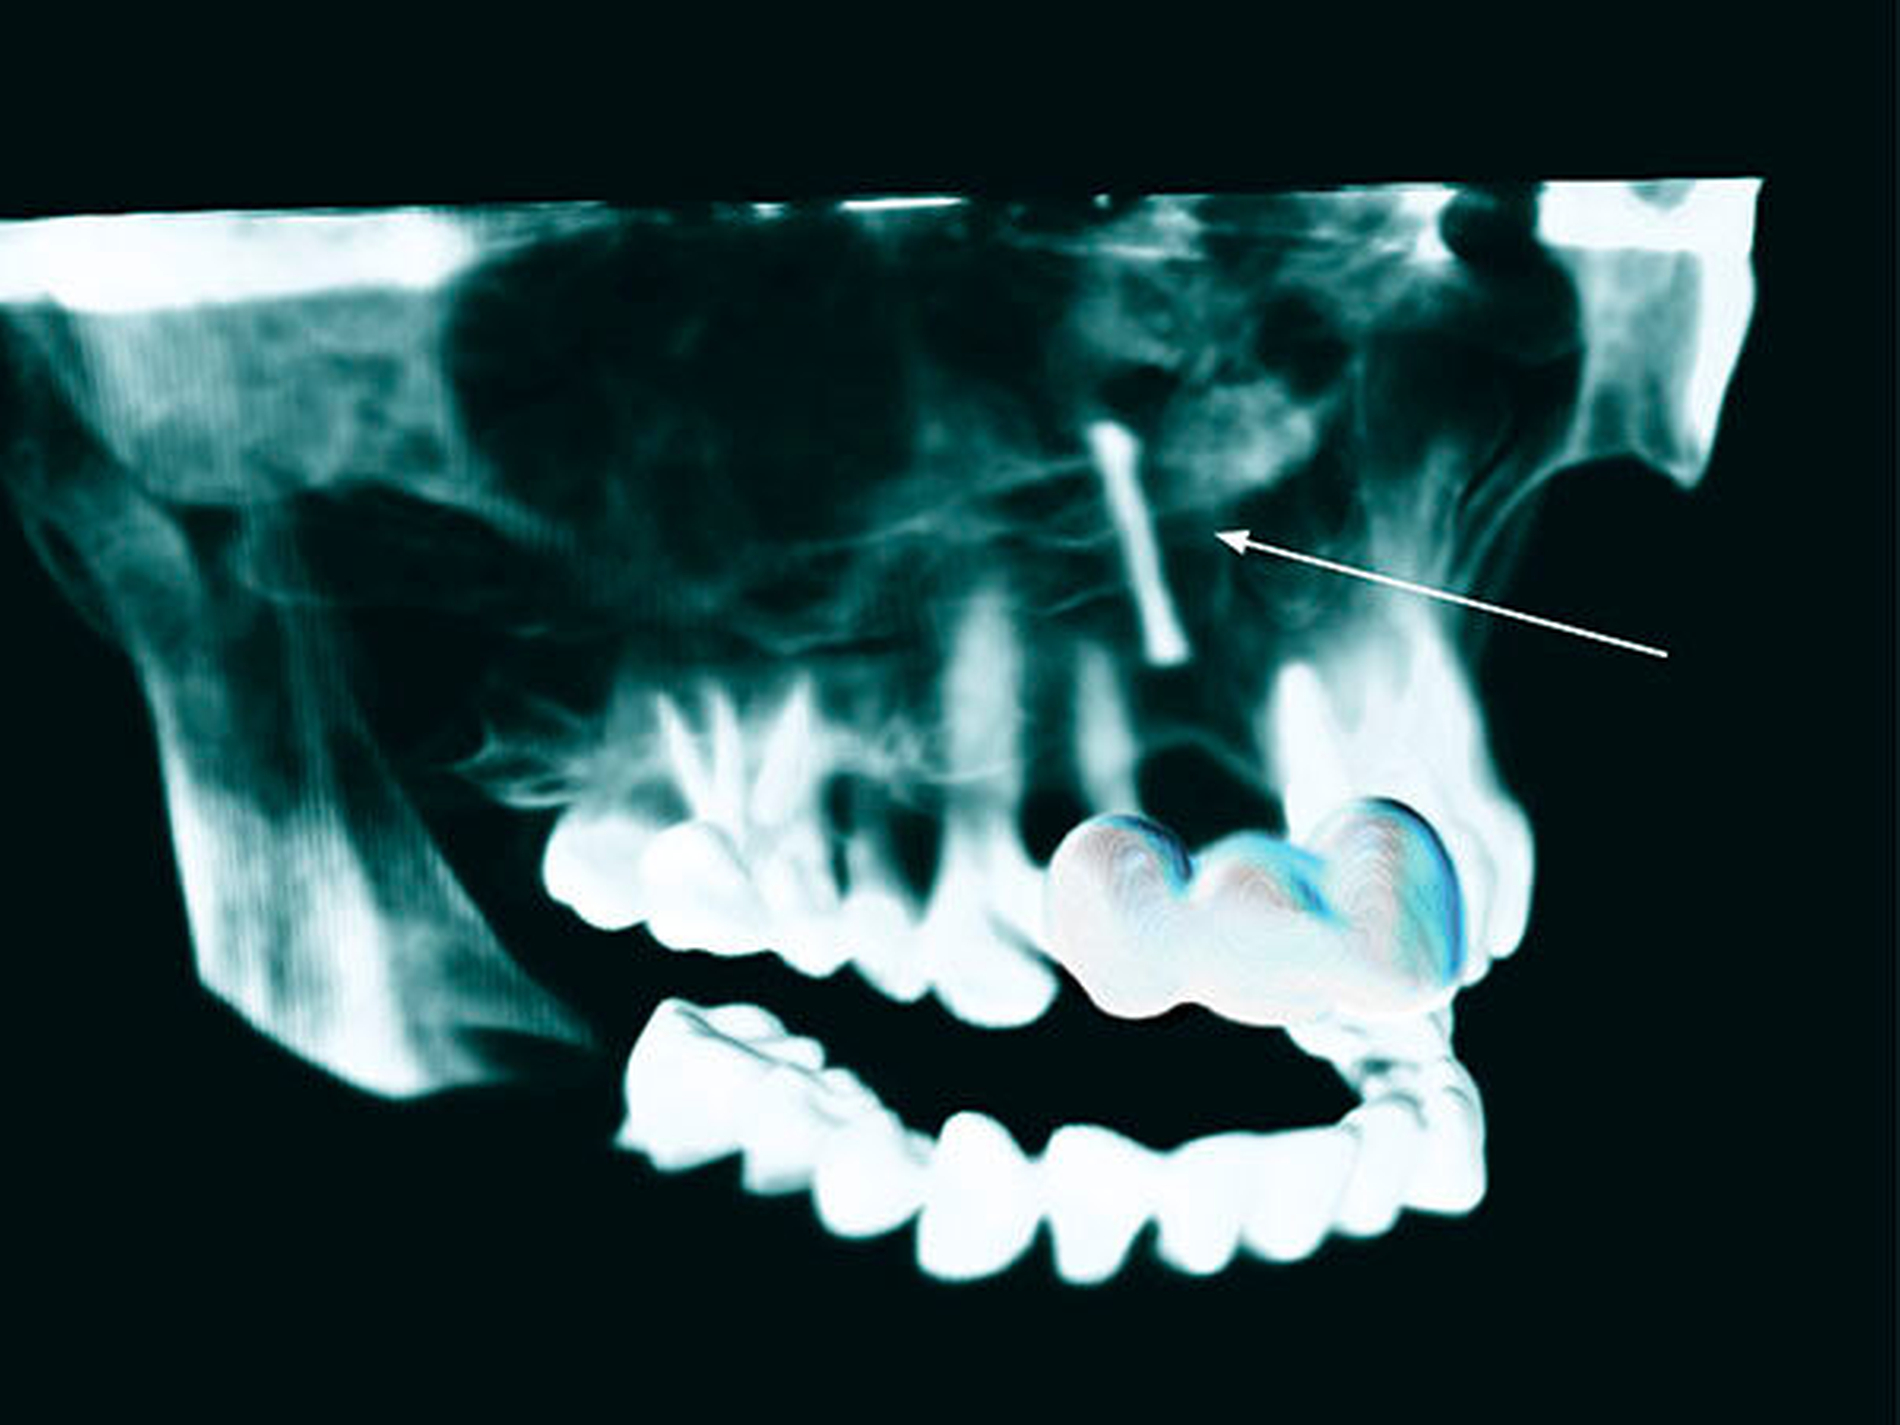

Eine 48-jährige Frau stellte sich in unserer Abteilung vor, nachdem ihr Zahnarzt im OPG einen Fremdkörper apikal der Alveole von Zahn 11 (Abbildung 1) diagnostiziert hatte. Das Röntgenbild wurde im Zuge einer angestrebten Implantatplanung in Regio 11 angefertigt. Bis dato war die Patientin mit einer Brücke von 12–21 in der Oberkieferfront versorgt, nachdem sie im Alter von neun Jahren Zahn 11 bei einem Sturz verloren hatte. Nach eigenen Angaben habe man damals versucht, den Zahn zu replantieren. Nach vorübergehendem Erfolg der Reinsertion des Zahns sei dieser nach einiger Zeit allerdings wieder verlustig gegangen. Es erfolgte die Versorgung mit einer provisorischen, später mit einer definitiven Brücke. Über den Vorgang der Replantation, die Verwendung eines Wurzelstifts oder den Verbleib des Stifts im Oberkiefer war der Patientin nichts bekannt. Im Zuge der Implantatplanung wurde ein DVT angefertigt, das den Verdacht eines Fremdkörpers, weit apikal der ursprünglichen Insertionslokalisation, bestätigte (Abbildungen 2 und 3).

Im vorliegenden Fall kam es nach retrograder, extraoraler Aufbereitung des Zahns und anschließender Stiftinsertion zur Ersatzresorption des Zahns mit Verbleib des Keramikstifts im Oberkieferknochen. Da die Patientin das Trauma im jungen Alter erlitt, unterlag die Maxilla in den folgenden Jahren dem physiologischen Knochenwachstum. Der verbliebene Stift folgte passiv dem Oberkieferwachstum und fand – mit dem kranialen Anteil – seine endgültige Lage im Bereich des Nasenbodens (Abbildung 6).